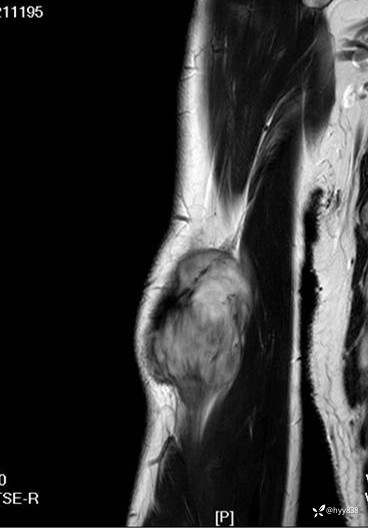

SAG T1WI+PDWI fs

COR T2WI